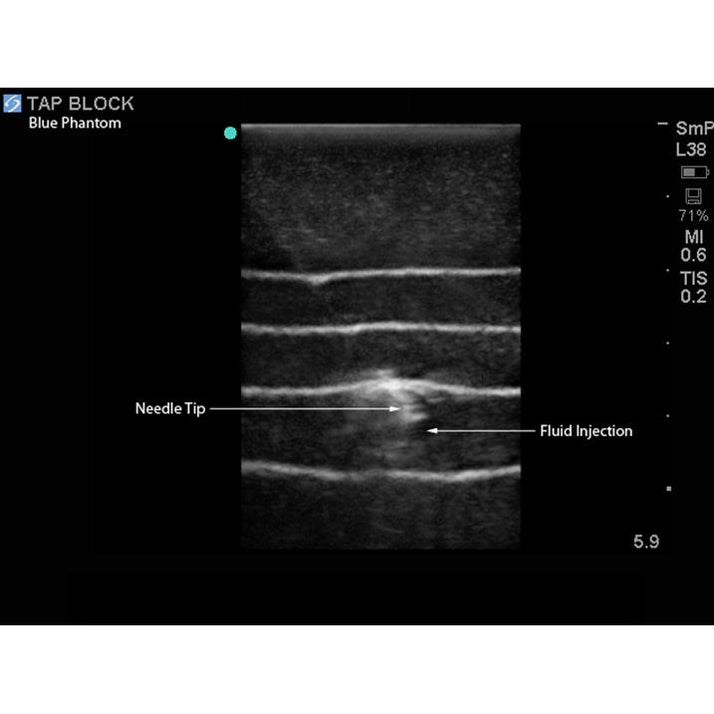

From www.researchgate.net

Process of TAP block as seen on ultrasound examination Download How Long Does Tap Block Last Liposomal bupivacaine does not appear to extend the duration of the tap. Depending on the type of medicine used, a tap block will usually last for 12 to 36 hours. The tap block targets the nerves derived from the anterior rami of thoracolumbar spinal nerves (t6 to l1) as they pass through. When performed with ropivacaine, the tap block has. How Long Does Tap Block Last.